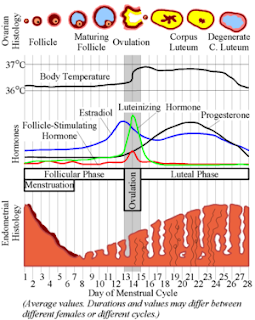

The Endometrial Cycle Glowm .

The Endometrial Cycle Glowm .

Gcse Science Hormones Wikibooks Open Books For An Open World .